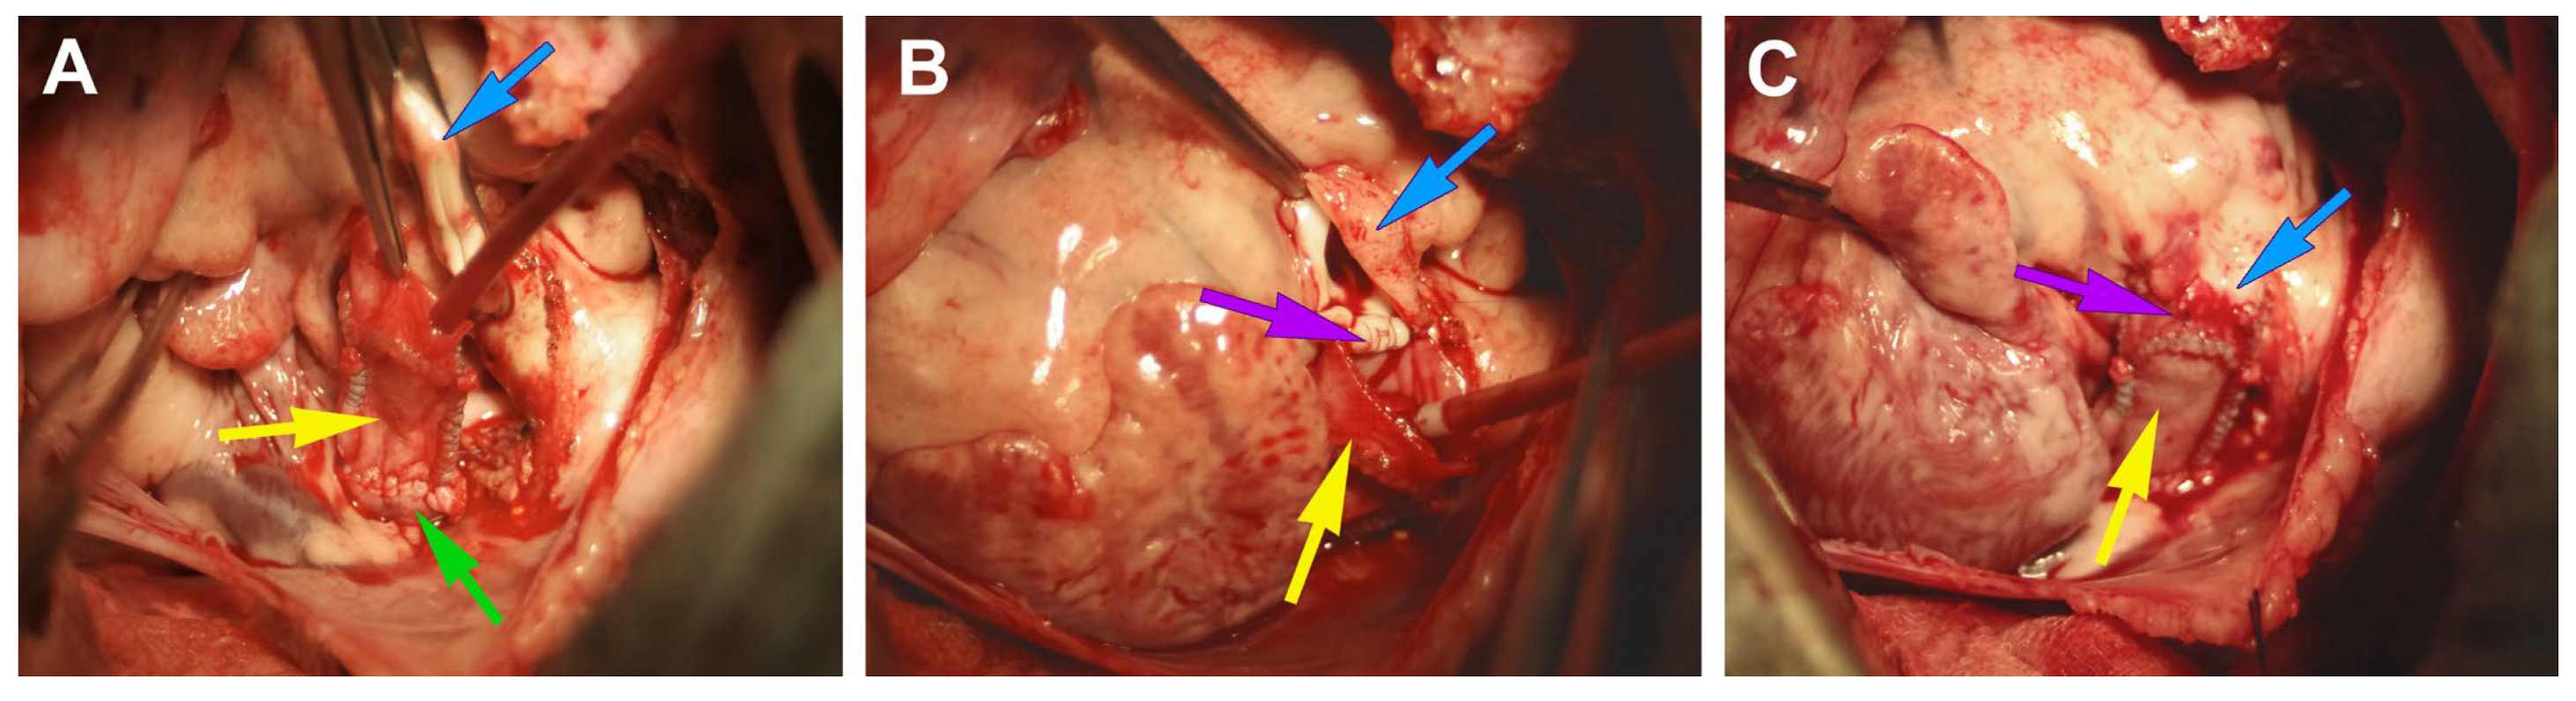

2.3. Conduit Implantation